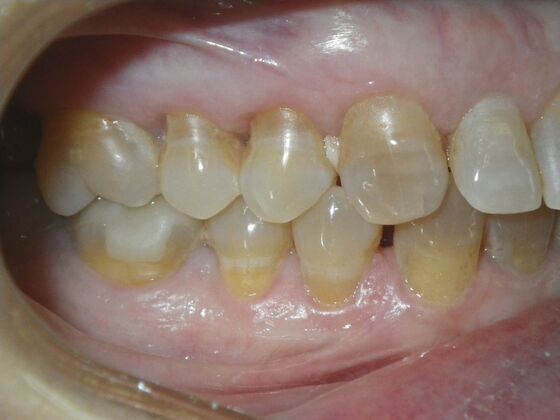

Cosmetic Changes with Veneers and Crown and Bridge: Case 1

Patient presented with spacing between upper central incisors and dark tetracycline stains that she wanted corrected